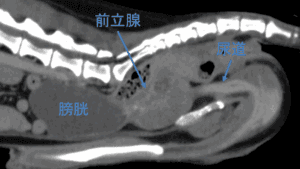

犬の肛門周囲で最も発生が多いのが肛門周囲腺腫です。肛門周囲腺腫は良性腫瘍であり、犬の肛門に輪状に存在する肛門周囲腺という腺組織が腫瘍化したもので、肛門以外にも包皮、尾などにも散在しています。肛門嚢は、肛門の4時方向および […]